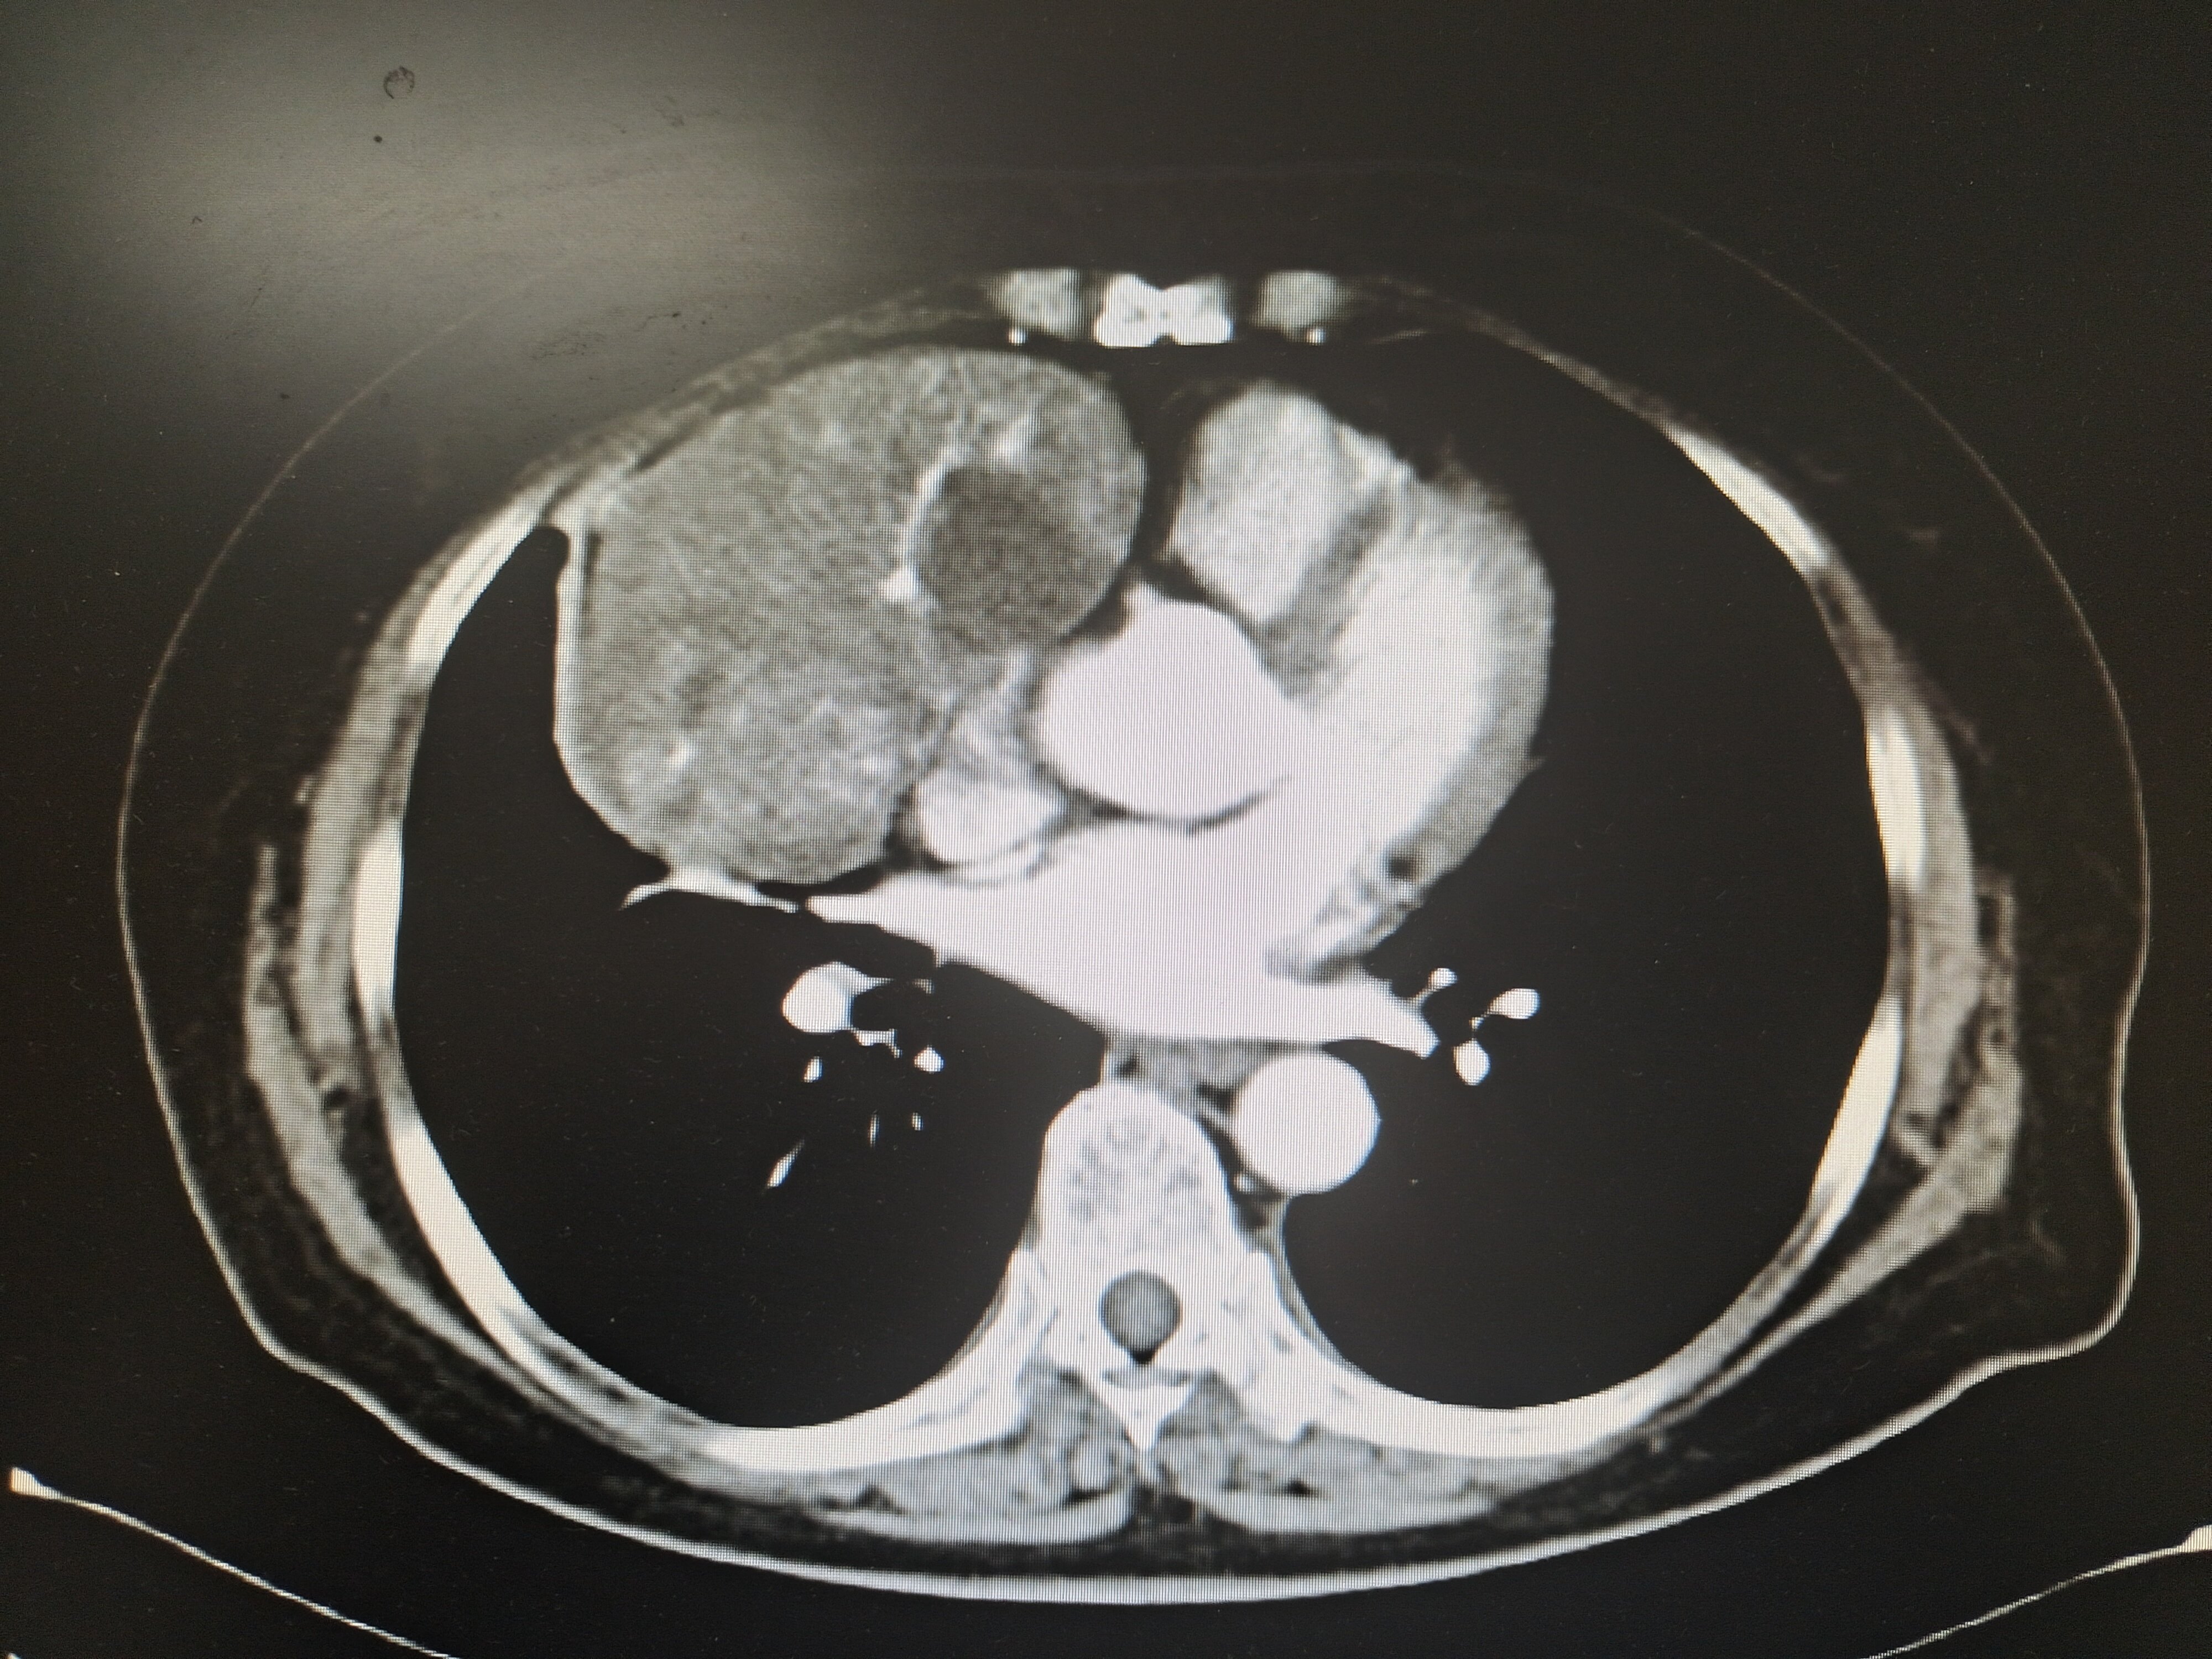

增强 CT 是纵隔肿瘤最重要的影像评估手段,既能够显示出肿瘤的形态,又能够揭示肿瘤的血供情况及其与周围血管的毗邻关系。如有必要,还可根据增强 CT 进行三维重建。对于疑似血管源性肿瘤或纵隔肿瘤侵犯、压迫大血管,也可采用血管造影进一步评估。